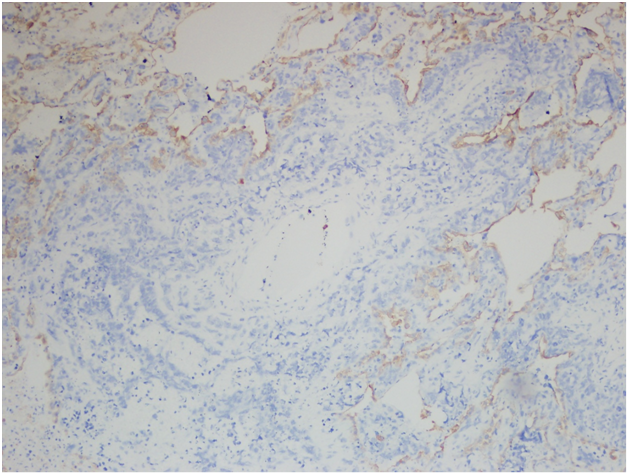

However, the wedge resection of the right lower lobe revealed angiosarcoma with lymphovascular invasion. This biopsy showed highly atypical and large malignant cells with increased mitoses (Figure 2A&2B). The immunohistochemical stains showed diffuse positivity for CD31, CD34, and vimentin (Figures 3A-3C). Stains for AE1/AE3 (Figure 3D), cam5.2, TTF-1, desmin, and OCT3/4 were negative. Along with the clinical history, a final diagnosis of angiosarcoma of the heart with metastases to the lungs was made.

Figure 3D Right lower lobe wedge resection. Immunohistochemical stain for AE1/AE3, 400x.